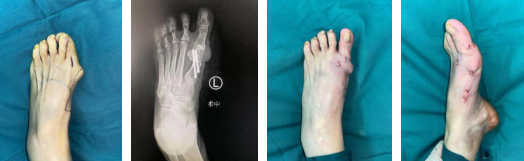

74岁女性,发现左足拇外翻畸形10余年

术前(左一)术中(左二)术后即刻(右一、右二)